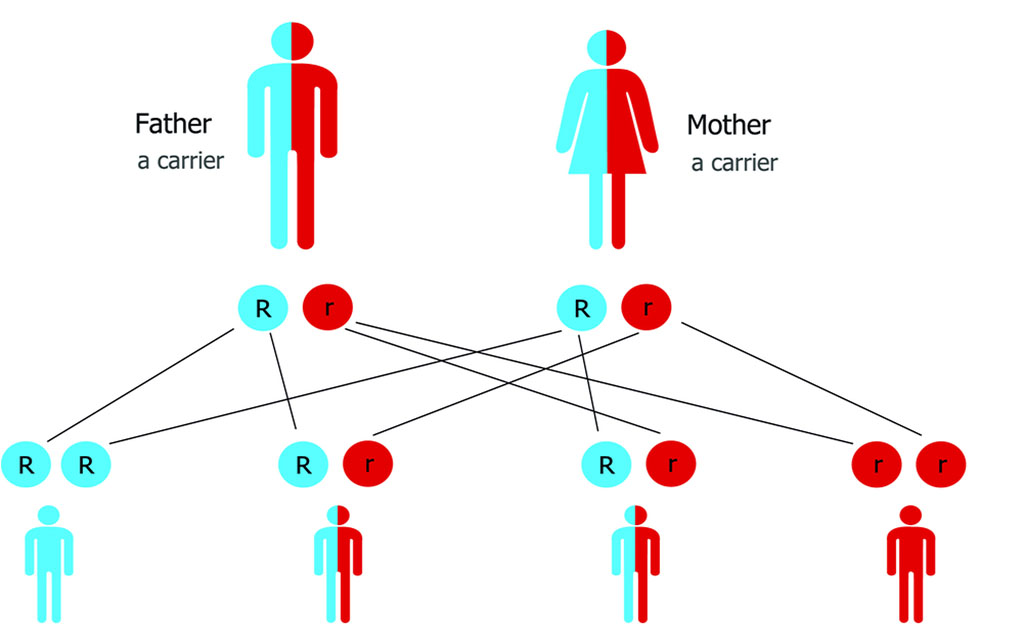

থ্যালাসেমিয়া প্রতিরোধে বিয়ের আগে হবু দম্পতির টেস্ট করানো কতটা জরুরি?

0 SHARES Share Tweet রাহেলা জামান বেশ কয়েক দিন ধরে লক্ষ্য করছেন যে, ইদানিং থ্যালাসেমিয়া নিয়ে বেশ কথা হয়। রাহেলা থ্যালাসে...